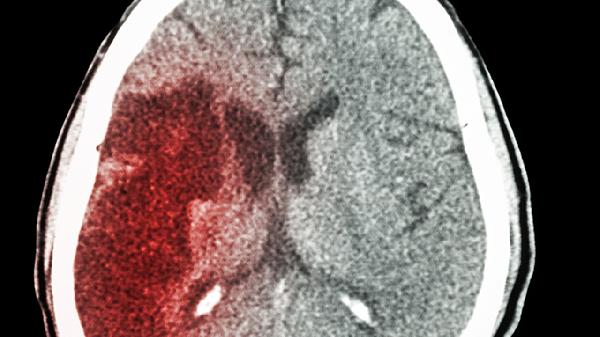

摔跤导致脑出血可能引发颅内压增高、神经功能损伤、意识障碍、继发感染及生命危险。脑出血的危险性主要与出血量、部位、年龄及基础疾病等因素相关。

脑出血后血液积聚在颅腔内,可能压迫脑组织导致颅内压升高。颅内压增高会引起剧烈头痛、喷射性呕吐、视乳头水肿等症状。严重时可形成脑疝,直接压迫脑干生命中枢,需紧急通过脱水治疗或手术清除血肿。

出血部位不同可造成对应功能区损害。基底节区出血常导致偏瘫、偏身感觉障碍;小脑出血易引发共济失调、眩晕;脑干出血可能出现瞳孔异常、呼吸循环衰竭。神经损伤程度与出血量呈正相关,部分患者会遗留永久性功能障碍。

大量出血或关键部位出血可能直接威胁生命。脑干出血死亡率达50%以上,丘脑出血易破入脑室系统引起急性梗阻性脑积水。出血量超过30毫升或中线移位超过1厘米时,保守治疗死亡率显著升高。